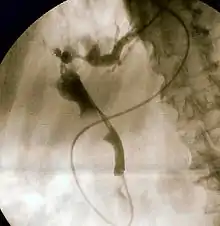

![]() صورةٌ لتنظيرٌ الإثناعشر، وتظهرُ قيحًا يخرجُ من أمبولة فاتر، مما يُدلل على التهاب الأقنية الصفراوية صورةٌ لتنظيرٌ الإثناعشر، وتظهرُ قيحًا يخرجُ من أمبولة فاتر، مما يُدلل على التهاب الأقنية الصفراوية | |

يُعتبر تصوير البنكرياس والأقنية الصفراوية بالتنظير الباطني بالطريق الراجع (ERCP) الاختبار المعياري الذهبي للانسداد الصفراوي، حيثُ يتضمن استخدام التنظير الداخلي (تمرير أنبوبٍ عبر الفم نحو المريء، ثم المعدة حتى يصل إلى الاثناعشر) لتمرير قنيةٍ صغيرةٍ نحو قناة الصفراء، وبعد ذلك تُحقن مادةٌ مظللةٌ لتعتيم القناة، ثُم تؤخذ صورة بالأشعة السينية لمطالعة مشهدٍ مرئيٍ للجهاز الصفراوي. يُمكن أحيانًا في صورة التنظير الدخلي للأمبولة مُشاهدة بروزٍ من لأمبولة لحصوةٍ صفراوية في القناة الصفراوية المشتركة أو ظهورٌ واضحٌ للقيح من فتحة القناة الصفراوية المشتركة. تظهرُ الحصوات الصفراوية في الصور بالأشعة السينية (المعروفة باسم صور الأقنية الصفراوية) على شكل مناطق غير مُعتمة في مُحيط قناة الصفراء. استبُدل تصوير البنكرياس والأقنية الصفراوية بالتنظير الباطني بالطريق الراجع عمومًا بتصوير البنكرياس والأقنية الصفراوية بالرنين المغناطيسي لأغراضٍ تشخيصية. يُستخدم تصوير البنكرياس والأقنية الصفراوية بالتنظير الباطني بالطريق الراجع خطًا أولًا فقط في المرضى المُصابين بأمراضٍ خطيرة والذين لا يُمكن تأجيلهم لإجراء اختباراتٍ تشخيصية، ولكن على الرغم من هذا، إذا كان مؤشر الشك مرتفعًا حول وجود التهابٍ في الأقنية الصفراوية، فإنَّ تصوير البنكرياس والأقنية الصفراوية بالتنظير الباطني بالطريق الراجع يستخدمُ عادةً لتصريف انسداد القناة الصفراوية المشتركة.[2]